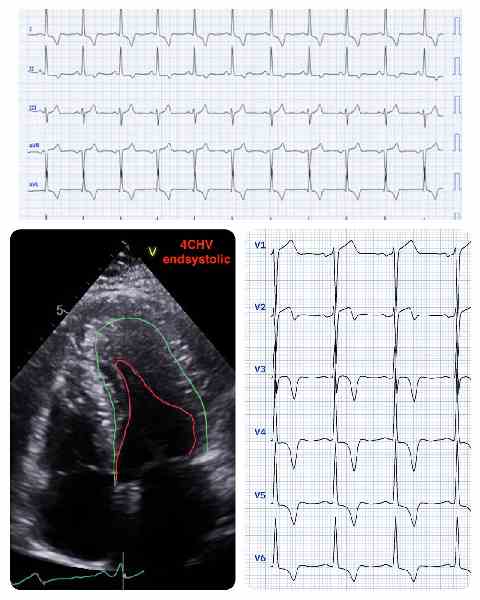

Image of the Week - 23 July 2025

Image of the week